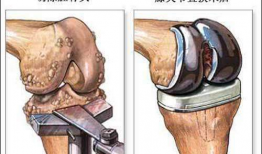

膝关节置换手术视频,从术前准备到术后康复

你有没有想过,当你的膝关节像老化的弹簧一样“嘎吱嘎吱”作响时,会有一种神奇的手术能把它换成一个全新的呢?没错,就是膝关节置换手术...